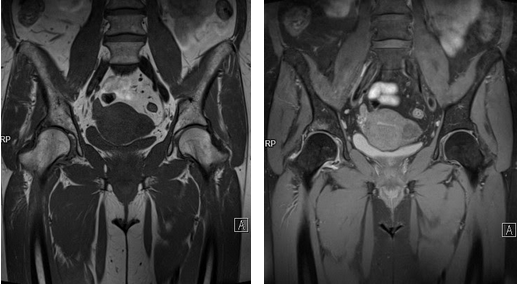

Рисунки 1,2. МР-картина артроза тазобедренных суставов с наличием отека костного мозга дистрофического характера в верхне-наружных отделах вертлужной впадины справа

Рисунок 3. МРТ тазобедренных суставов в косо-аксиальной плоскости.

Суставной хрящ головки бедренной кости и правой вертлужной впадины с обеих сторон однородной структуры, неравномерной толщины, целость его не нарушена. Головка бедренной кости сферичная, шейка не укорочена, не утолщена.